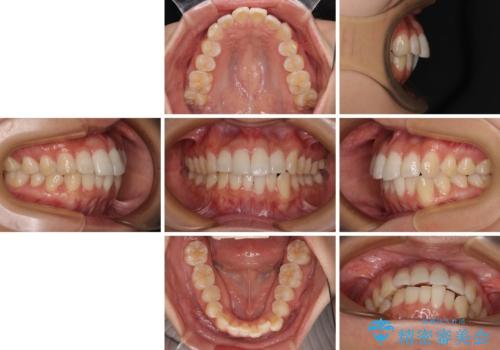

前歯のデコボコを治したい インビザライン矯正

- 上下前歯の叢生を気にして来院された患者様です。

インビザラインでの治療を希望されていて、デコボコの程度が中等度であり、安価なパッケージにて対応可能と判断されたため、インビザライン・モデレートを用いて矯正治療を行うこととしました。

インビザライン・モデレートは、製作できるアライナーの枚数に制限があるため、移動可能な量に限りがあるものの、インビザライン・ライトよりも枚数が多いため、幅広い症例に対応可能です。